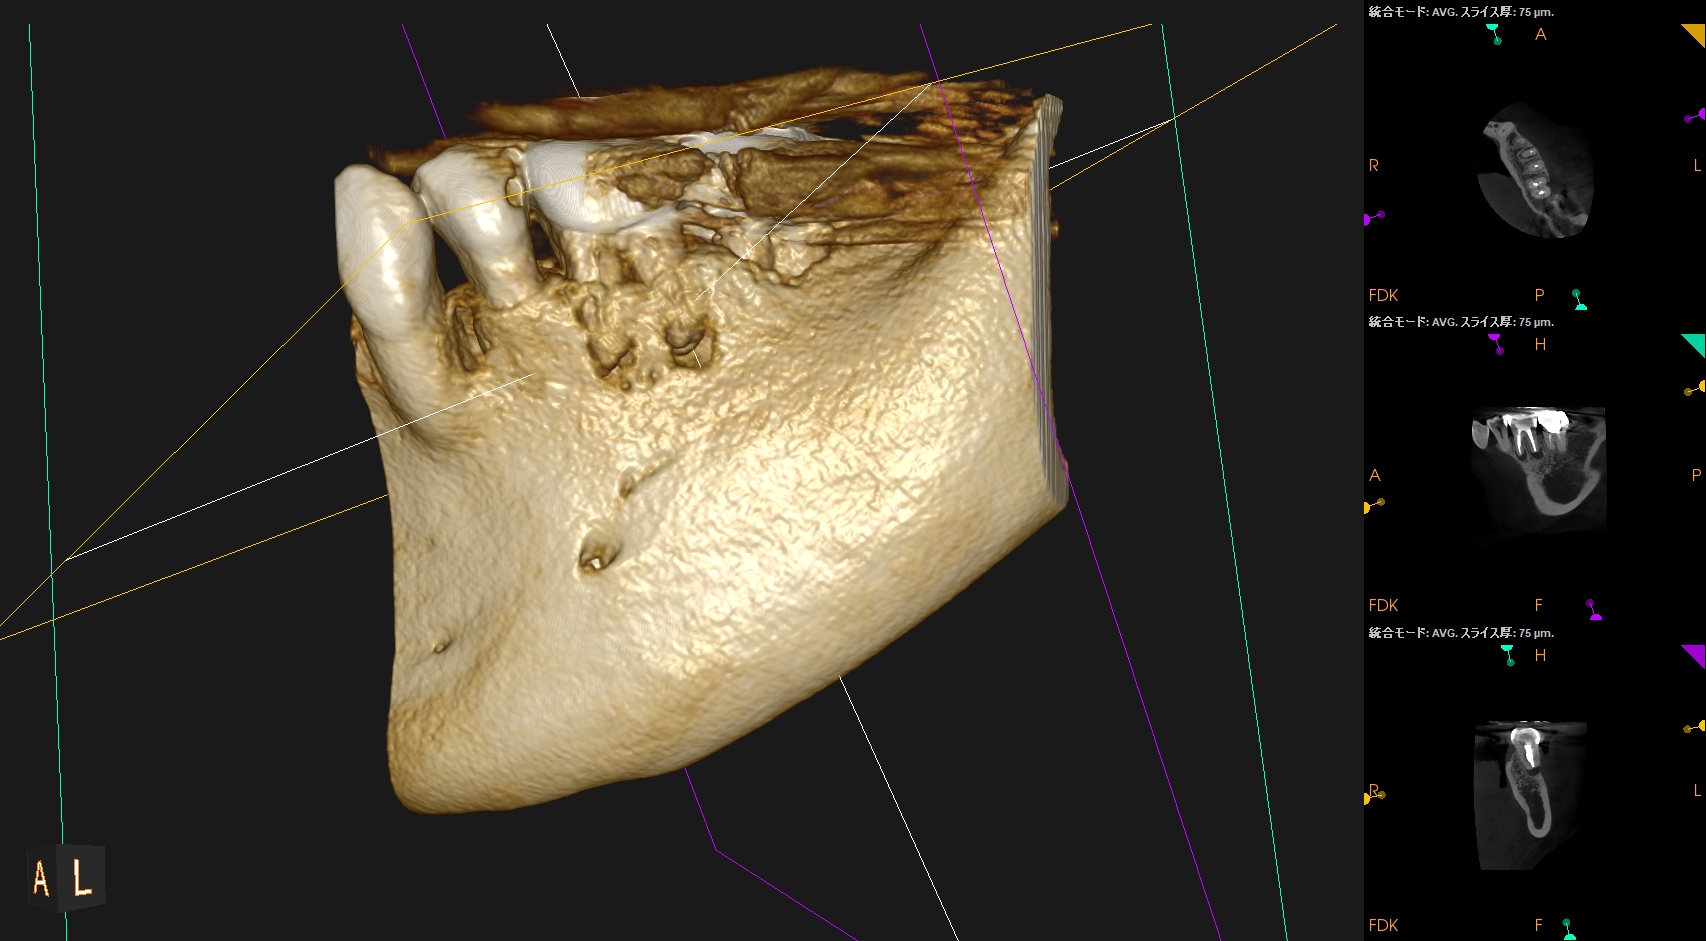

CBCT(2025.9.16)

MB

ML

D

MにもDにも病変がある。

B

頬側の骨がない。

これが圧痛に対する反応の原因だ。